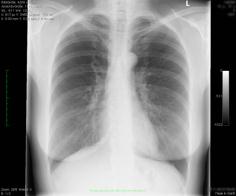

Ārsts pēc plaušu rentgenuzņēmuma izvērtē plaušu veselību.